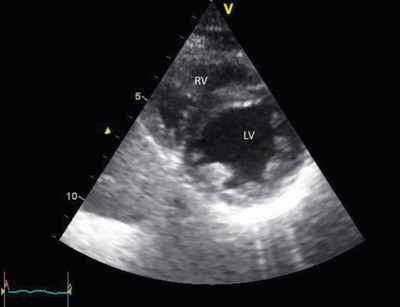

En 20 år gammel kvinne besvimte på stasjonen etter en cirka to timers togreise. I akuttmottaket var hun blek, satt høyt på båren, var uttalt motorisk urolig, dyspneisk og klaget over brystsmerter. Systolisk blodtrykk var 140 mm Hg, puls regelmessig ca. 80 slag/min og pulsoksimetri viste verdier < 85 % (SpO₂). Etter kort tid inntraff det sirkulasjonskollaps med pulsløs elektrisk aktivitet. Det ble startet basal hjerte-lunge-redning og etter 3–4 minutter var det følbar egenpuls i a. carotis, men ikke i a. radialis. Hun våknet til og var svært urolig, men kunne svare bekreftende på p-pillebruk. Pasienten pustet spontant, men ble støttet med 100 % oksygen på maske. SpO2 var <85 %, men det var usikker måling pga. dårlig perifer pulsasjon. Ekkokardiografisk undersøkelse ca. ti minutter etter innkomst viste en hyperkinetisk venstre ventrikkel med svært redusert fylling. Høyre ventrikkel var betydelig dilatert og hypokinetisk. Ventrikkelseptum bukte inn i venstre ventrikkel. Det var ingen tegn til perikardvæske eller hjertetamponade (fig 1). EKG viste sinustakykardi med frekvens 140 slag/min, QRS-bredde 0,12 mm, høyre grenblokk-morfologi med akse + 90°, ST-elevasjon 3 til ca. 10 mm i standardavledninger II, III, aVF samt V2-V4 og ST-depresjon 2 mm i standardavledninger I og aVL (fig 2). Ny sirkulasjonsstans inntraff ca. 15 minutter etter innkomst, og hun ble intubert og hjerte-lunge-redning kontinuert.

Ut fra alder, p-pillebruk, betydelig hypoksi og ekkokardiografiske funn vurderte vi lungeemboli som den mest sannsynlige diagnosen. Lungeemboli gir varierende grad av blodstrømobstruksjon gjennom lungearteriene. Dette kan gi redusert fylling (preload) til venstre ventrikkel, og ekkokardiografisk vil det kunnes påvises en hyperdynamisk og tom venstre ventrikkel (fig 1). Hjerteminuttvolumet vil reduseres og kunne føre til blodtrykksfall og sirkulasjonskollaps.

Ekkokardiografi viste tegn på en hemodynamisk signifikant lungeemboli. Det er vanlig å se de funn vi gjorde: dilatasjon av høyre ventrikkel, redusert høyresidig kontraktilitet, økt diameter av høyre ventrikkel i forhold til venstre ventrikkel og deviasjon av septum mot venstre side. Man kan også se dilaterte proksimale pulmonalarterier, endret blodstrøm i utløpstractus på høyre side, trikuspidalinsuffisiens med jethastigheter omkring 3–3,5 m/s og utvidet v. cava med redusert inspiratorisk kollaps. Pasienter med normal ekkokardiografisk undersøkelse vil ha mindre sannsynlighet for signifikant lungeemboli (4). Et isolert høyre ventrikkel-infarkt vil kunne gi liknende ekkokardiografiske funn, men vanligvis ikke en slik betydelig dilatasjon av høyre ventrikkel med tegn på økte systoliske trykk.